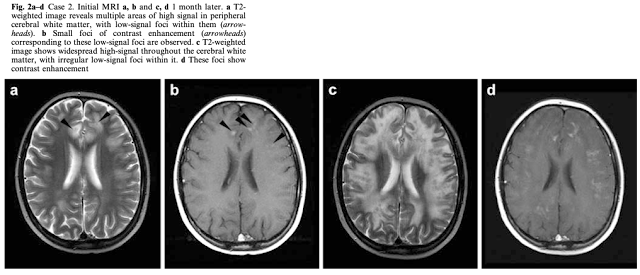

MTX白質脳症の評価にはMRIが有用

・典型的なのは左右対称性の白質病変で, 頭頂-後頭葉に多い

他に前頭葉, 脳幹, 基底核, 視床, 小脳, 脊椎など様々な部位に生じ得る

・画像からは, 血管性浮腫やBBBの破壊が予測されている

造影MRIでは造影されないことが多い

報告より画像をいくつか貼り付ける:

(Intern Med 50: 2219-2222, 2011)

(Neuroradiology (2003) 45: 493–497)